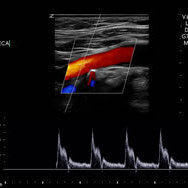

Vascular Screening

We recommend a vascular MOT for patient's over the age of 50. You check your teeth, your eyes, why not your veins & arteries too.